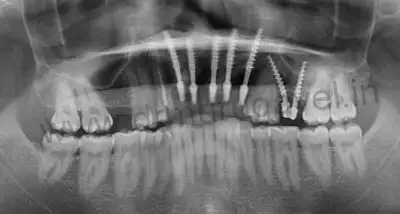

X RAY – before treatment

Dental implants in x ray

- It should be noted that his provisional bridge had hygienic gaps in the gum region , this denotes perfect gum healing and the implants condition was confirmed after taking radiographs ( OPG & CBCT ).